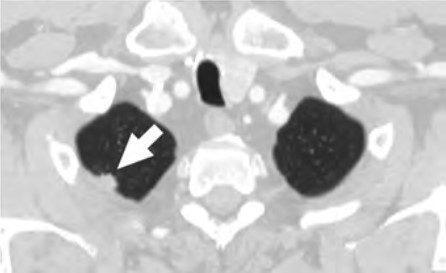

At the individual level, some of the barriers include decreased opportunities to provide accurate smoking history in the EMR, cost concerns related to insurance coverage of LCS and subsequent followups (Fig. 3), challenges to understanding LCS results when examinations show abnormal findings, fragmentation of care for management of abnormal LCS results and incidental findings, and difficulties navigating the complexities of health care systems [4, 8, 10]. Cost transparency and cost concerns are areas of active research, because cost influences how patients access and use health services [2]. For example, a recently published study evaluated the out-of-pocket cost of invasive procedures after LCS and showed that the rates of invasive procedures in commercially insured populations exceed those of invasive procedures in clinical trial participants [2].